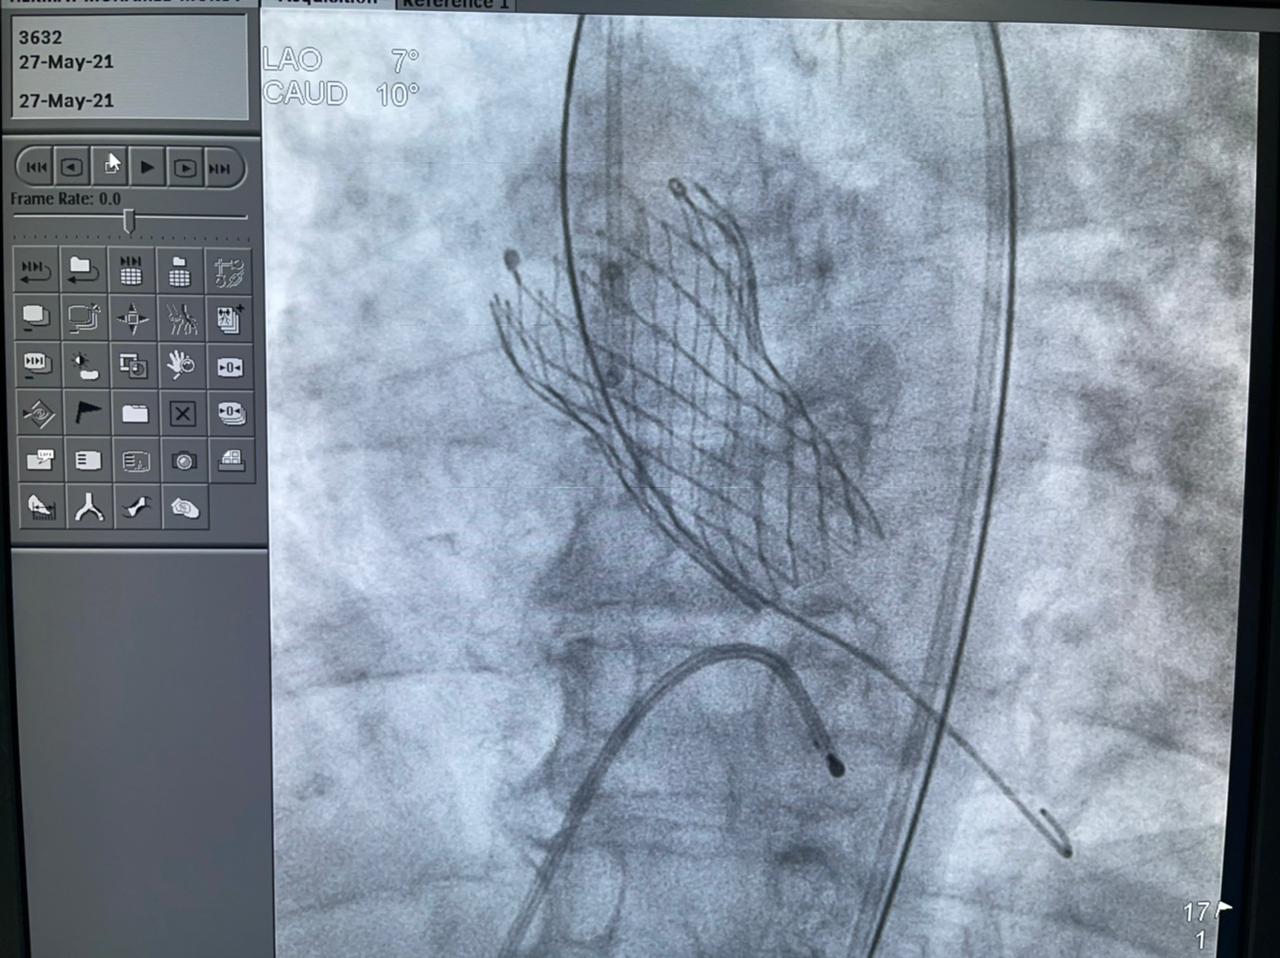

وأشارت الهيئة إلى أن الحالة الأولى من العمليات الدقيقة والمتطورة التي أجرتها مستشفى النصر التخصصي، كانت لمريض يبلغ من العمر 65 عامًا يعاني من ضيق شديد متكلس بالشريان التاجي الأيمن، بعد أن أجريت له جراحة قلب مفتوح منذ 15 سنة، وتم استخدام الشنيور الطبي لتوسيع الضيق، وتمت العملية بنجاح بالرغم من الصعوبة البالغة للحالة.

وتابعت الهيئة أنه قام بإجراء العمليات للمرضى الثلاثة في يوم واحد، فريق من أمهر الأطباء الأخصائيين والاستشاريين في علاج أمراض القلب والقساطر القلبية، يضم، الدكتور طارق رشيد أستاذ القلب والقسطرة وخبير حالات الانسداد المزمن للشرايين التاجية ورئيس قسم القسطرة القلبية بمستشفى النصر التخصصي، والدكتور ياسر صادق استشاري القلب وخبير القسطرة القلبية، الدكتور أمير البسطويسي استشاري جراحة القلب والصدر، الدكتور أحمد شبل استشاري القلب والقساطر التداخلية، الدكتور محمد علم الدين استشاري القلب والقسطرة العلاجية، الدكتور محمد لبيب استشاري جراحة الأوعية الدموية، وإخصائي علاج أمراض القلب والأوعية الدموية الدكتور معتز سلامة و الدكتور محمد عطا، أخصائي علاج أمراض القلب والقسطرة العلاجية الدكتور مصطفى رفعت، الدكتور أحمد عبد الرؤوف أخصائي التخدير بالمستشفى.